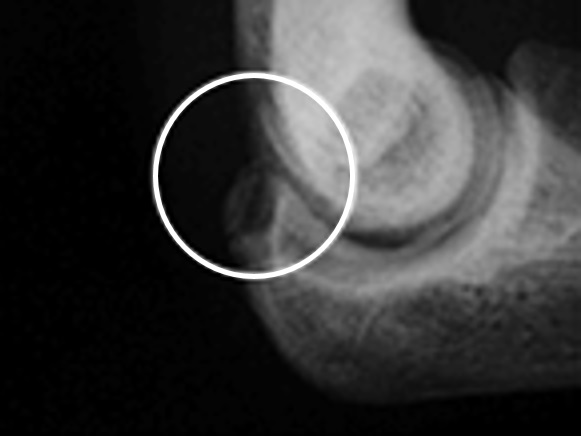

野球肘は名前のごとく、野球によるスローイング動作、特に成長期の投手に多く発生するオーバーユース(使いすぎ)に起因し、投球側の肘の①内側(図1)、②外側(写真1)、③肘頭(写真2)に発生する投球時の疼痛が主症状であるスポーツ障害です。徐々に発症する場合が多く、慢性化しやすいため肘の疼痛が出現したら注意を要します。投球動作の加速期(acceleration)は肘関節屈曲、外反、前腕回外位をとります。内側型は肘の内側部が投球動作時に回内屈曲筋によって牽引力が加わり、回内筋群や内側側副靱帯、尺骨神経がストレッチされ、内側に微細損傷が発生します。重症例では上腕骨内側上顆〈じょうか〉骨が牽引力によって剥離骨折を起こします。外側型は逆に肘外側にある上腕骨小頭や橈骨〈とうこつ〉頭に圧迫力が加わり、骨の壊死〈えし〉、欠損、遊離体などの離断性骨軟骨炎が発生します。後方型は減速期(follow-through)に肘伸展位で、尺骨肘頭に牽引力が加わり剥離や疲労骨折などの変化をきたします。

写真2 肘頭型:尺骨肘頭に骨の離開像を認める

上記症状に、レントゲンでの骨変化を認めます。内側型では上腕骨内側上顆の骨肥厚、骨端線離開、回内筋部への骨遊離像を、外側型では上腕骨小頭や橈骨頭の骨変形、欠損、遊離骨片の存在を、後方型では尺骨肘頭の亀裂骨折、疲労骨折像を認めます。